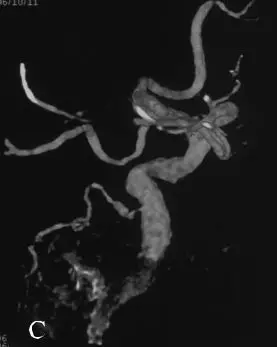

C:右侧颈内动脉造影三维重建;

DSA:急诊行全脑血管造影提示基底动脉下段可见1枚形态不规则囊性动脉瘤(图18-3B)。三维重建后提示基底动脉下段开窗畸形,动脉瘤瘤颈位于开窗近段分叉处,瘤顶有子囊(图18-3C),动脉瘤瘤颈1.85 mm,瘤深5.45 mm,瘤宽2.77 mm。左侧椎动脉造影提示左侧椎动脉仅供血小脑后下动脉(PICA)区域,未汇入基底动脉(图18-3D)。颈内动脉造影未见明显异常。

C:右侧椎动脉造影及3D重建见基底动脉下段开窗畸形并开窗近段分叉处动脉瘤;

D:左侧椎动脉造影提示左侧椎动脉发育不良,仅供血小脑后下动脉(PICA)区域。